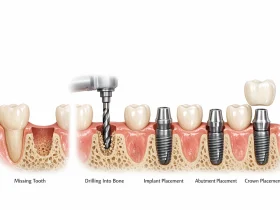

ایمپلنت دندان یکی از ماندگارترین راهکارها برای جایگزینی دندان از دست رفته است و بسیاری از بیماران ...